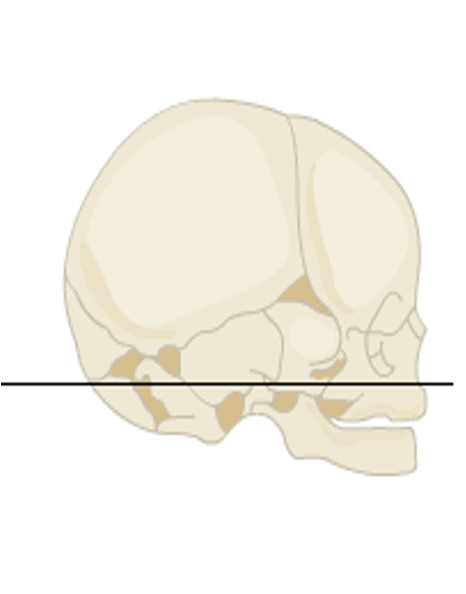

outline the skull at birth

sutures

6 fontanelles (posterior, anterior, x2 sphenoid, x2 mastoid)

define cranial vault

cranial vault: the part of the skull that encloses or protects the brain i.e. calvaria, skullcap

what is the function of fontanelles

fontanelles give the skull flexibility as it goes through the birth canal